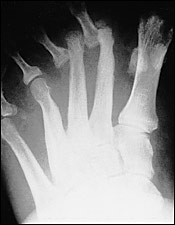

神經性關節病變可分為兩類:萎縮型atrophic及肥厚型hypertrophic,萎縮型通常位於足部前端forefoot,並且在蹠骨遠端distal metatarsals造成骨頭溶解,使得蹠骨遠端的頭部及幹部變形,在X光下看起來像鉛筆尖或被吸吮過的聖誕節柺杖糖sucked candy cane如圖一。

圖1. 骨溶解,蹠骨遠端